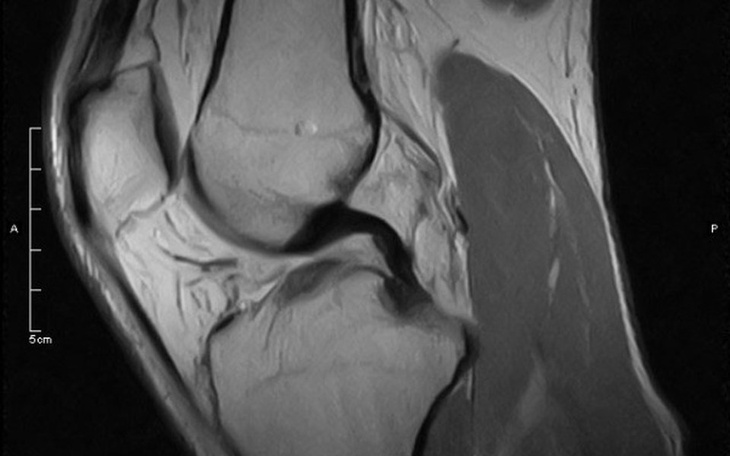

No i stało się Kochani, rezonans tylko potwierdził zerwane więzadło acl. Bez rekonsrukcji ani rusz. Pewnie mówicie - co trzeci człowiek też ma zerwane....., może i tak, ale ja potrzebuję operacji. Pewnie mówicie - inni też jej potrzebują....., pewnie tak, ale ja nie mam pieniędzy na operację.